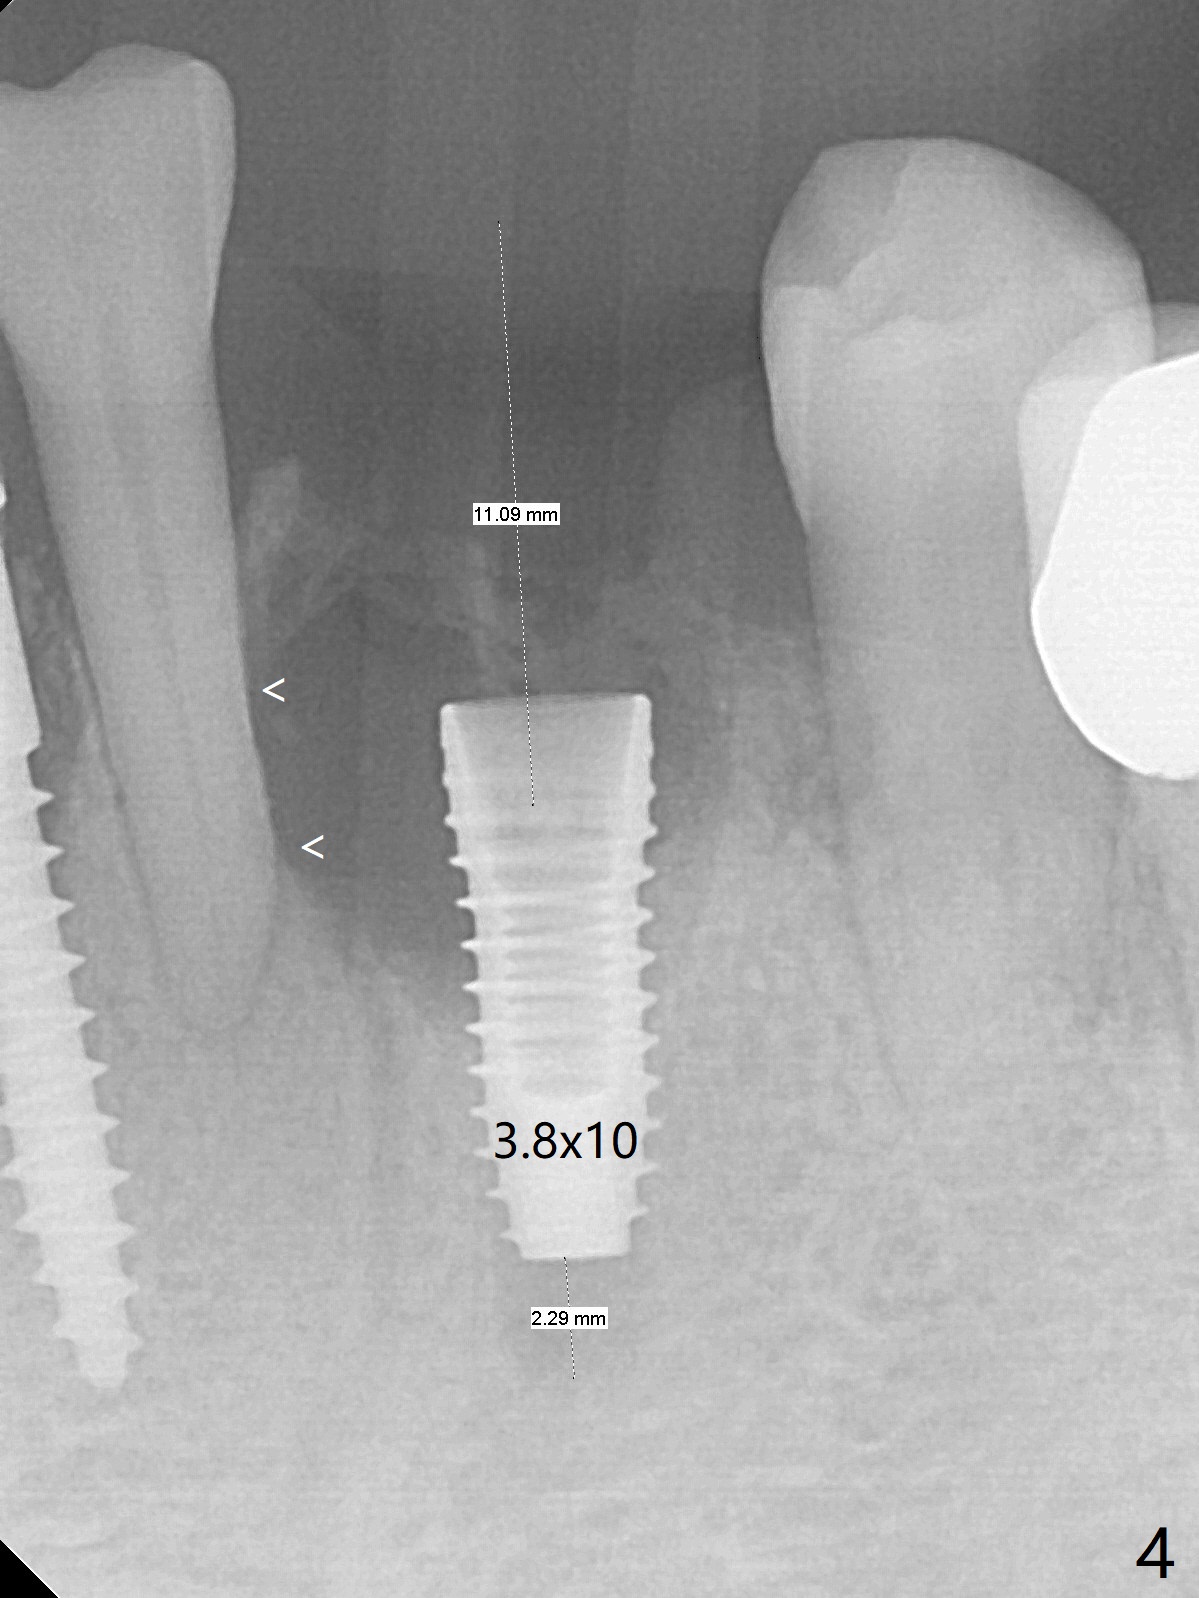

There is a fistula buccal to the apex of the tooth #23 preoperatively (Fig.1), which is related to loss of the buccal plate of the socket of #23. Therefore an implant is placed mainly in the socket of #22 (Fig.3). The lingual (Fig.2 L) gingiva appears to have more extensive inflammation. After extraction, the lingual (Fig.3 L) gingival margin is significantly lower than the buccal one. The lingual crest is ~ 4 mm lower than the buccal one. A 3.8x10 mm dummy implant is placed tentatively with an apical space (Fig.4). When a same dimension definitive implant is placed with 40 Ncm, it is 2 mm below the lingual gingival margin, whereas 6-7 mm below the buccal one (Fig.5). Vanilla graft is placed before placement of a 5.5x4(5) mm abutment (Fig.6,7). There is a 2-3 mm lingual (L) gap to be filled with the allograft secondarily to prevent periimplantitis (Fig.7). Later the abutment is changed to a longer and smaller one (Fig.8) with more of the allograft (*). After trimming of the abutment (Fig.9 (*: papilla between the fused teeth)), an immediate provisional is fabricated to close the socket (Fig.10, similar to Fig.1). The majority of the bone graft seems to be in place 8 months postop (Fig.12). The implant appears to have been placed buccal, consistent with the thin and slightly erythematous buccal gingiva (Fig.13). The ridge completely regenerates 2 years post cementation (Fig.14).